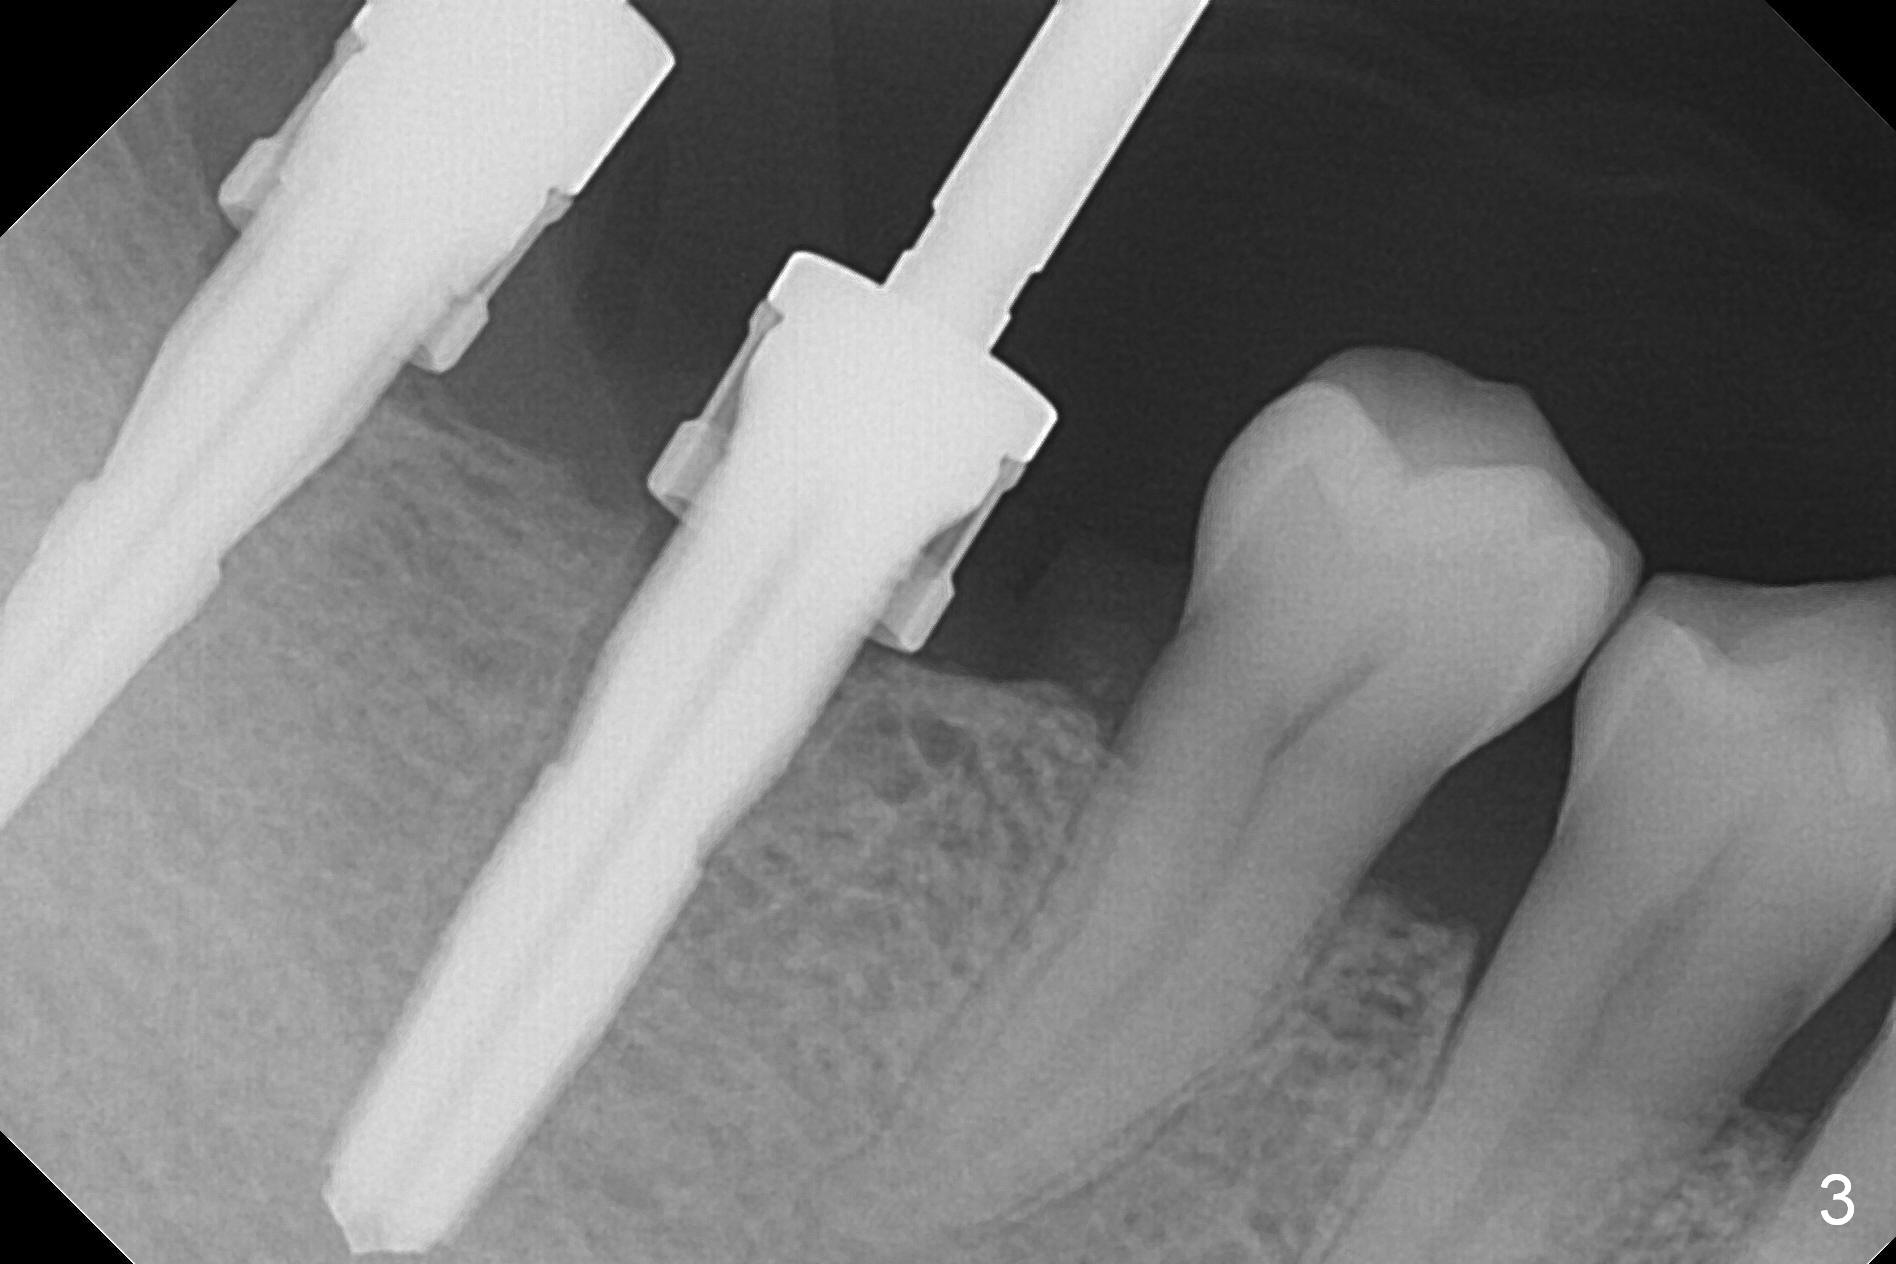

The supraerupted tooth #2 is adjusted using the lower right surgical stent. Osteotomies are initiated by using starter drill through surgical stent over the ridge (Fig.1) prior to incision. The initial depths are 10 and 12 mm at the sites of #31 and 30, respectively (Fig.2). The new sensor with the existing sensor holder cannot reach the deep portion of the lingual vestibule (Fig.2,3). Without the sensor holder, the #2 sensor with rounded corners has no problem showing the Inferior Alveolar Canal (Fig.4 red dashed line). The two implants (5x12 and 5x14 mm, Fig.5) are placed with >50 Ncm. Cemented abutments are immediately placed (6.8x4(2) and 6.8x4(3) mm) to reduce suture tension (after autogenous bone graft and collagen dressing) and hold periodontal dressing in place. The wound does not heal completely 15 days postop (Fig.6). The patient reveals that he smokes 1/2 pack per day. There is crestal bone resorption 4 months postop (Fig.7 *). It appears that for smokers, implants should be smaller, placed deeper and buried. In addition, his oral hygiene is not good.